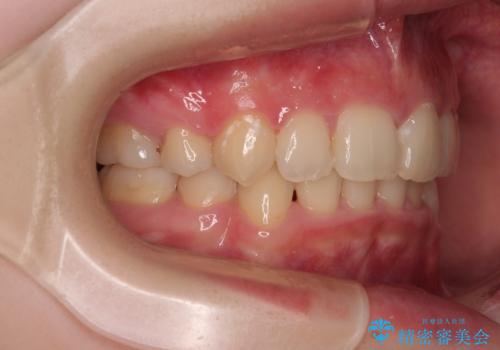

【モニター】デコボコと隠れてしまう前歯 ワイヤー装置による抜歯矯正で美しい口元に

- デコボコになっている前歯を気にして来院された患者様です。

口元の突出感は気になっていないものの、デコボコを解消すると口元が前方に突出する可能性があるため、上下左右の第一小臼歯4本を抜歯して、ワイヤー装置にて矯正治療を行うこととしました。

下の前歯が隠れてしまうほど深く咬みこんでいたため、上顎前歯が前方に突出しているような印象がありましたが、咬み合わせが改善され、整った口元に仕上げることができました。